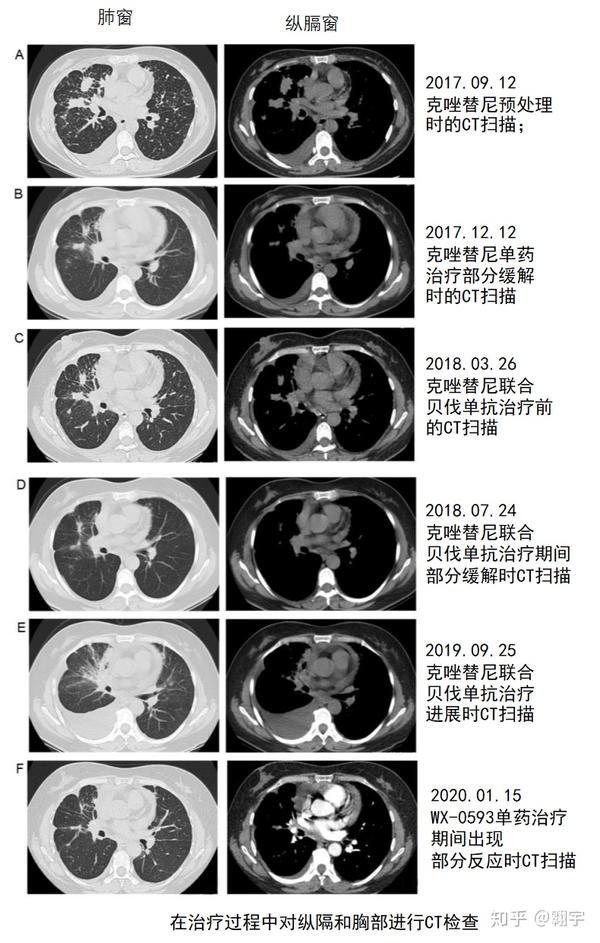

lungcancer案例特殊的alk基因融合让非小细胞肺癌患者实现长期生存